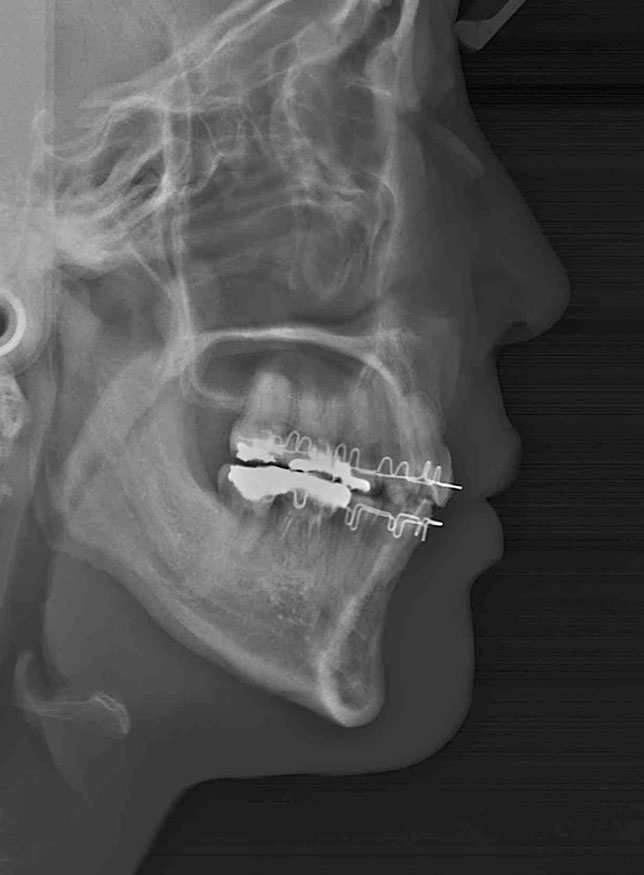

治療後の変化

再生治療により、

2~3ミリ下がっていた歯ぐきが回復。

歯の長さが自然なバランスに戻り、

厚みのある丈夫な歯ぐきが再建されました。

奥歯6本の再生治療を行ったケースでは、

虫歯予防という機能面の改善も期待できます。